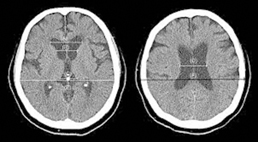

除了臨床的表徵外,主要的診斷工具為腦部的電腦斷層掃瞄或核磁共振檢查。在醫學影像上會發現腦室擴大,或合併有較大的側邊腦溝(如圖一),臨床上若遇疑似病案,通過影像檢查及臨床症狀判斷,可初步懷疑是水腦症 (possible hydrocephalus),若欲進一步提升診斷,可加做腰椎穿刺測試(lumbar tapping test)測量腦脊髓液壓力並先體外引流20-30 ml 左右的脊髓液,若病人有獲得改善,則其診斷的確定性增加為極像水腦症(probable hydrocephalus),此時病人若接受腦脊髓液分流管裝置手術後有持續性的進步,則可確診為水腦症(definite hydrocephalus),這是常壓性水腦症診斷的特別之處。

圖一、醫學影像上會發現腦室擴大或合併有較大的側邊腦溝

圖片來源:https://healthjade.net/ventricles-of-the-brain/.